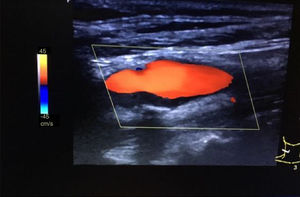

En la exploración física el paciente se encuentra consciente, orientado en tiempo y espacio. Presión arterial: 130/80mmHg, FC: 90lpm. Auscultación cardiopulmonar: RsCsRs, murmullo vesicular conservado. No se ausculta soplos en región abdominal. Neurológico: no focalidad neurológica. Se realiza ecografía en nuestro centro de salud (CS) objetivando placa en carótida interna derecha: hipoecogénica, heterogénea y calcificada (sombra posterior) que ecográficamente parece un trombo (fig. 1). Nos comunicamos con CV del hospital de referencia y comentamos los diferentes hallazgos, a continuación es remitido para realización de ecografía de troncos supraaórticos reglada donde se objetiva el mismo hallazgo que la ecografía realizada en nuestro CS, la angio-TAC informa como placa de ateroma en carótida interna derecha que provoca una estenosis del 70% (fig. 2). Se realiza TAC cerebral y aortoilíaco, sin alteraciones. Al paciente se le mantiene en tratamiento con estatinas de alta potencia y con antiagregantes plaquetarios.